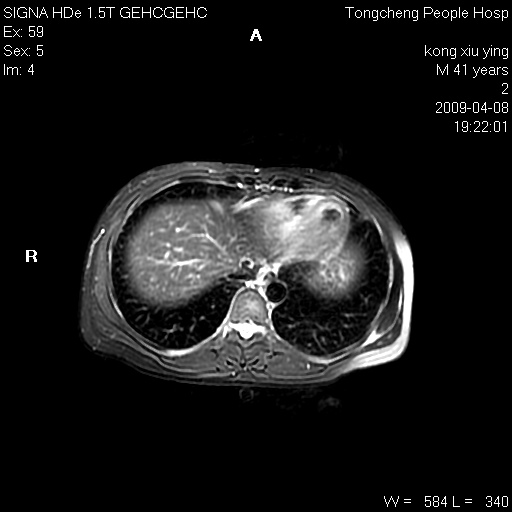

标题: CL1008:【经典】胆囊石榴籽样结石。 [打印本页]

标题: CL1008:【经典】胆囊石榴籽样结石。

女,41岁。健康体检——彩超提示:胆囊显示不清。平素健康,无不适感。

腹部mr扫描及mrcp,图像如下: